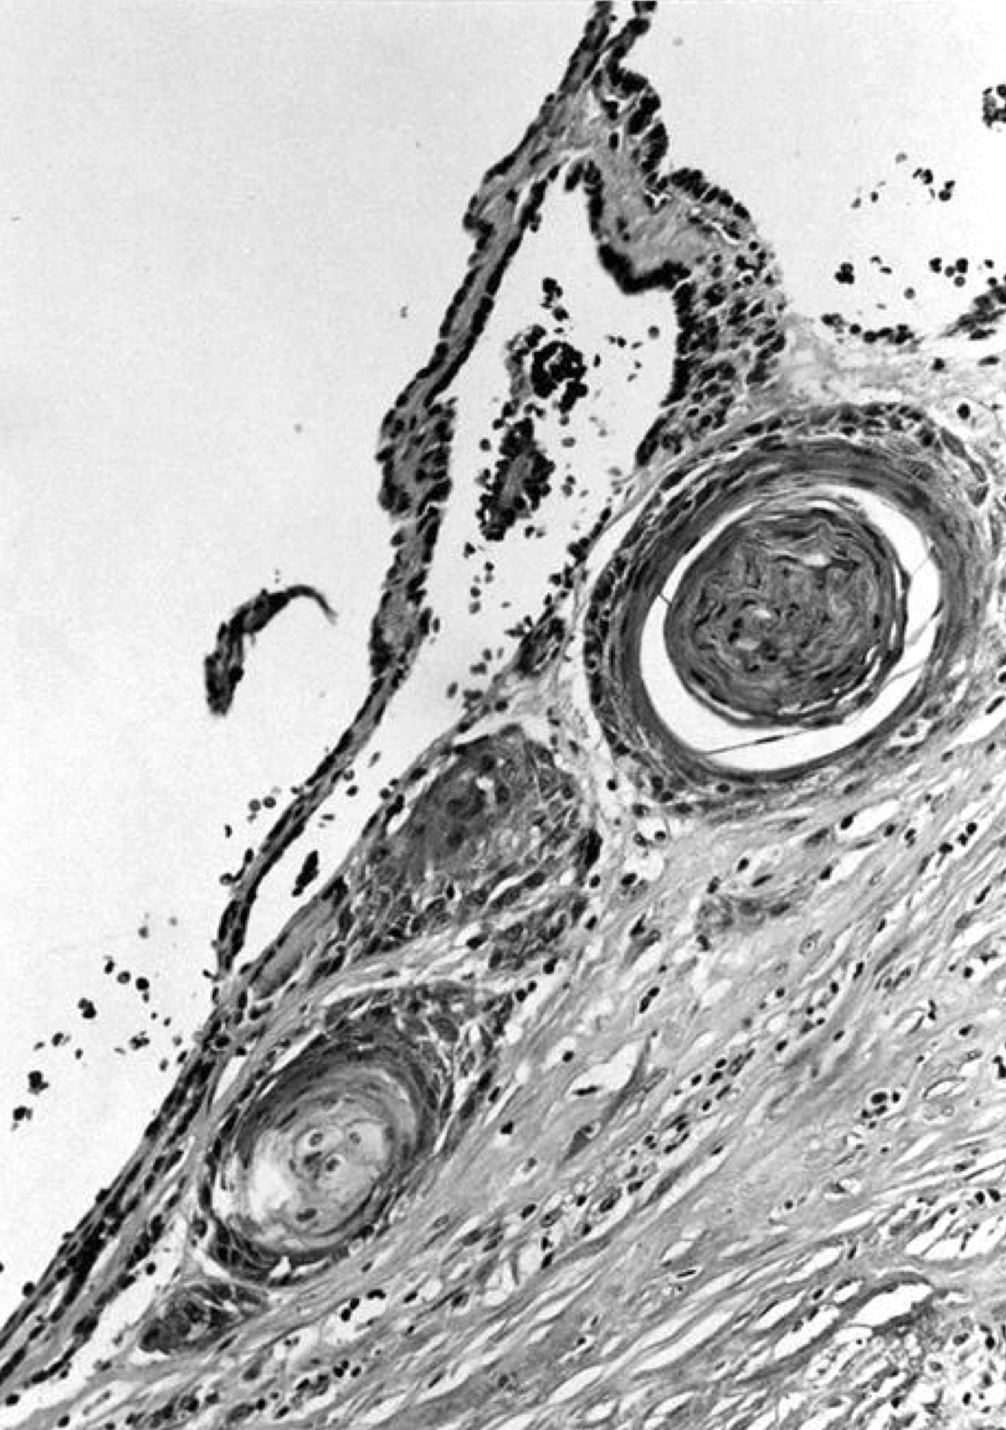

Microscopic (histologic) description

- Secondary changes may be seen, including foci of fresh or old hemorrhage, rupture of follicles with granulomatous response, fibrosis, calcification and even osseous metaplasia

- Some of the cystically dilated follicles may show papillary projections (Sanderson polsters) that may mimic papillary carcinoma; however, they lack the nuclear features of papillary carcinoma

Microscopic (histologic) images

Contributed by Swati Satturwar, M.D., Andrey Bychkov, M.D., Ph.D. and Rajeshwari K. Muthusamy, M.D.

AFIP images

C. Variably sized follicles with flattened hyperplastic epithelium, cysts, hemorrhage, granulomatous response, fibrosis, calcification or osseous metaplasia. Nodules may or may not be present in nodular goiter but generally lack a thick capsule. Prominent features are variably sized dilated follicles with flattened hyperplastic epithelium. Secondary changes include foci of fresh or old hemorrhage, rupture of follicles with granulomatous response, fibrosis, calcification and even osseous metaplasia. Some of the cystically dilated follicles may show papillary projections (Sanderson polsters). Cytologic atypia in the form of highly atypical nuclei occurs in patients exposed to radioactive substances.